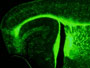

La testostérone et ses dérivés pourraient constituer un traitement efficace contre les maladies de la myéline telles que la sclérose en plaques. C'est ce que montrent les travaux réalisés par des chercheurs du Laboratoire d'imagerie et de neurosciences cognitives de Strasbourg (CNRS/Unistra), en collaboration notamment avec l'unité "Neuroprotection et neurorégénération : molécules neuroactives de petite taille" (Inserm/Université Paris-Sud).

La myéline compose les gaines qui protègent les fibres nerveuses et permettent d'augmenter la vitesse de l'influx nerveux. Un déficit dans la production de la myéline ou bien sa destruction conduit à de graves maladies pour lesquelles il n'existe actuellement aucun traitement curatif.